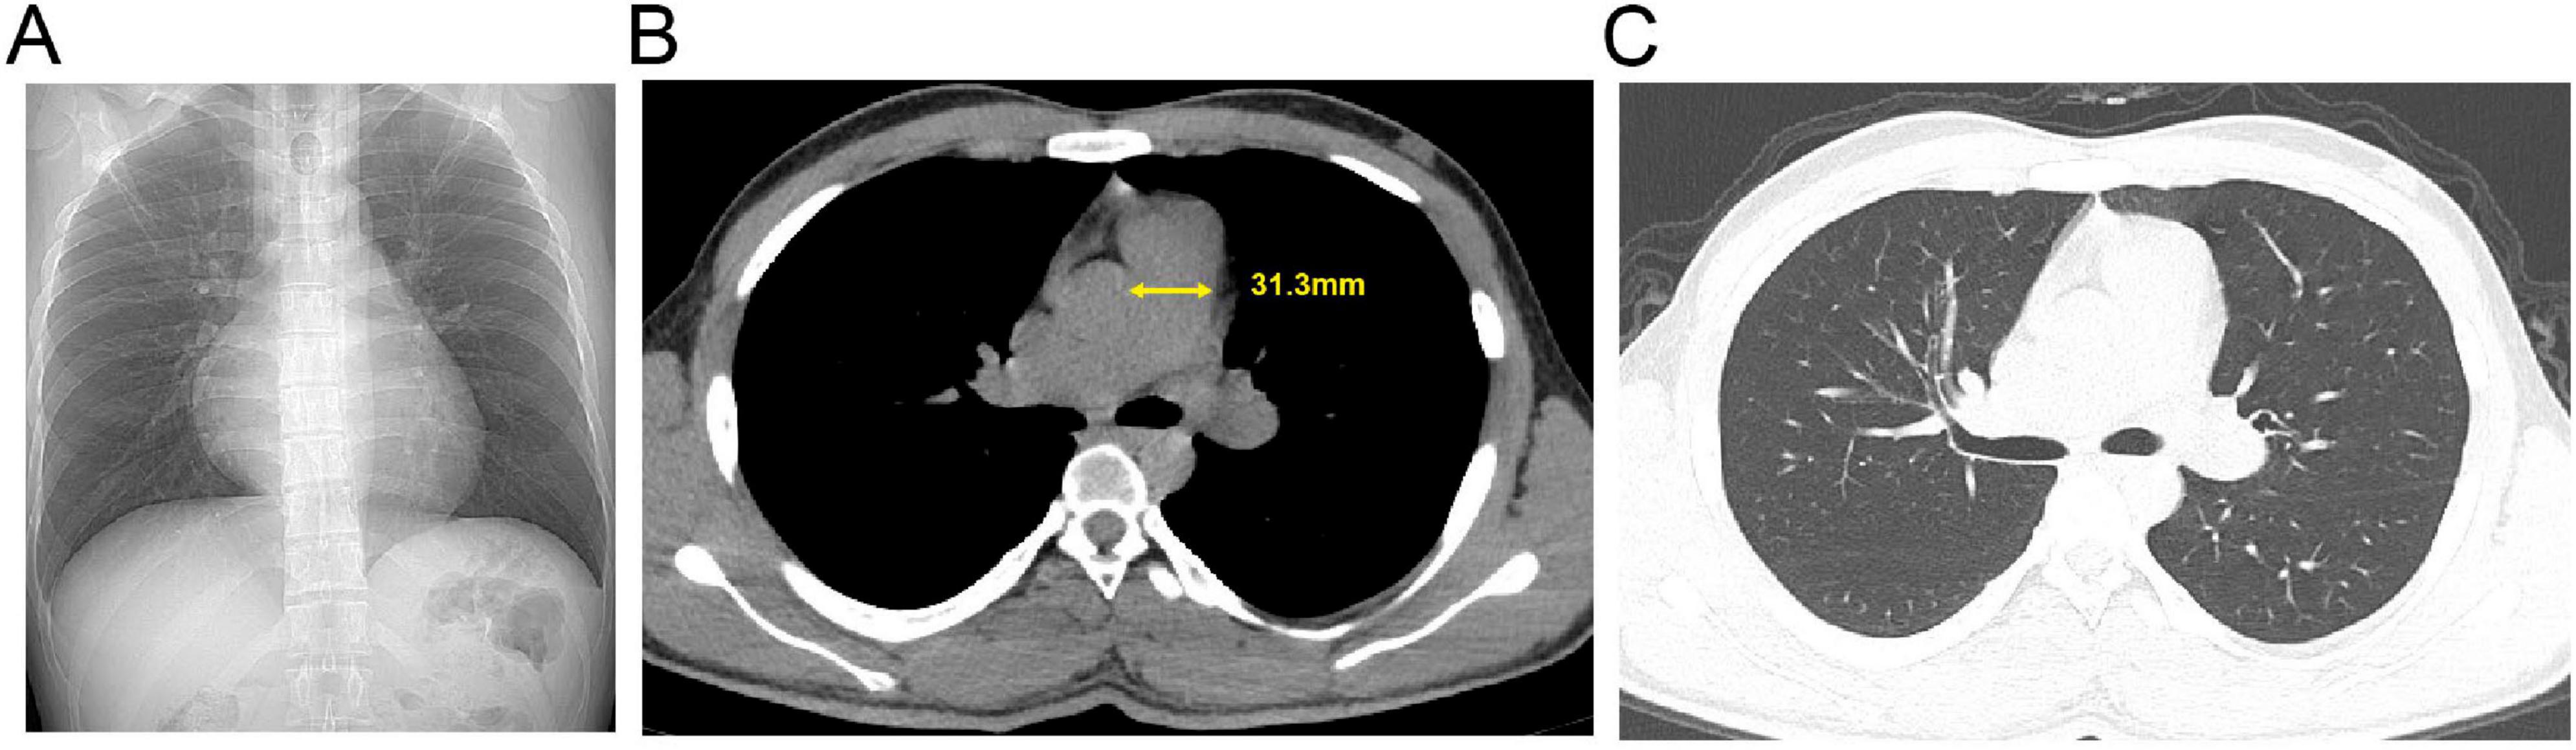

Background: The high-altitude environment characterized by hypobaric hypoxia can cause significant damage to the cardiovascular system, particularly vascular endothelial function, and is a significant trigger for acute and chronic mountain sickness. High-altitude pulmonary hypertension (HAPH) is a serious complication induced by prolonged exposure to high altitude, characterized by abnormally elevated pulmonary artery pressure and increased right heart load, which can progress to right heart failure and be life-threatening. This article aims to enhance clinicians' understanding of this disease through two cases of HAPH in young males. Case Description: Case 1 was a 21-year-old male who developed progressively worsening chest pain, shortness of breath, and amaurosis fugax after living at an altitude of 4800 meters for 4 months. Case 2 was a 20-year-old male who experienced exertional dyspnea accompanied by amaurosis fugax and a brief loss of consciousness after 18 months of residence at 4300 meters. Both patients were previously healthy with normal cardiopulmonary function before moving to high altitude. Physical examination upon presentation revealed significant hypoxemia (oxygen saturation 80% and 82% on room air, respectively). Echocardiography in both cases clearly demonstrated right atrial and right ventricular enlargement, moderate tricuspid regurgitation, with estimated systolic pulmonary artery pressures (sPAP) as high as 55 mmHg and 56 mmHg, respectively. Chest CT confirmed right heart enlargement and main pulmonary artery dilation. After systematic evaluation excluded other etiologies, HAPH was diagnosed. Discussion: The core pathophysiology of HAPH is hypoxia-induced pulmonary vasoconstriction and remodeling. These cases demonstrate that even for young, healthy individuals, prolonged exposure to extremely high altitudes can lead to severe pulmonary hypertension and right ventricular dysfunction. Diagnosis requires a combination of high-altitude exposure history, clinical symptoms, evidence of hypoxemia, and echocardiographic findings. The most fundamental treatment for diagnosed HAPH patients is removal from the high-altitude hypoxic environment, making early recognition and intervention crucial. Conclusion: The high-altitude environment poses a serious threat to the cardiovascular systems of susceptible individuals. For patients with a history of high-altitude residence who present with relevant symptoms, clinicians should maintain a high index of suspicion for HAPH and conduct timely screening and diagnosis to prevent adverse outcomes.